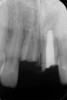

The patient's endodontic examination revealed a flexible splint from teeth Nos. 7 through 10 (Figure 1). Tooth No. 8 had a 3 mm x 3 mm class II fracture of the mesioincisal portion of the crown. Tooth No. 9 had a class IV fracture of the crown running labiopalatally from the remaining 2 mm of the crown to bone level on the palatal. A pulpotomy had been performed on the exposed pulp. Both teeth exhibited class III mobility. Teeth Nos. 7 through 10 did not respond to cold testing. None of the teeth were tender to palpation, and only tooth No. 9 had a slight positive response to percussion. Periodontal probings of tooth No. 8 were 4 mm to 5 mm on both the labial and palatal aspects. There was a narrow 12 mm probing on the straight palatal of No. 9; the remaining probing depths were 4 mm to 5 mm.2 A periapical radiograph showed both teeth Nos. 8 and 9 to have incompletely formed roots with wide-open foramina (Figure 2).

Fig 2. Age 8. Radiograph of teeth Nos. 8 and 9 at initial examination.

Figure 2